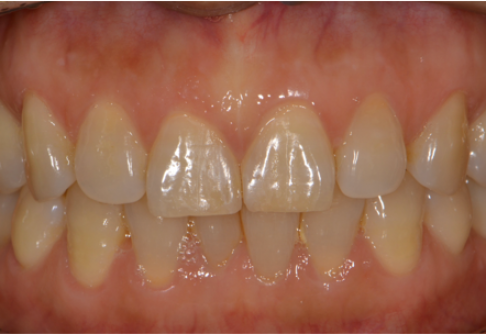

Before

After

위 치료 사례는 굿프렌즈치과에서 직접 치료를 받은 환자 분의 사례로 직접 동의를 얻어 게재되었습니다.